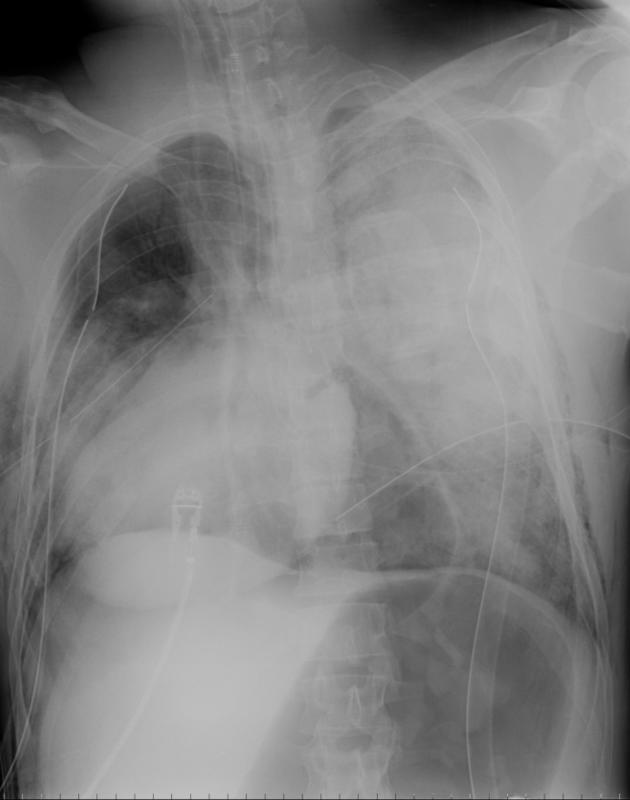

Gallery Blunt Chest Trauma BCT-Other Cardiac torsion post BCT

Cardiac torsion post BCT